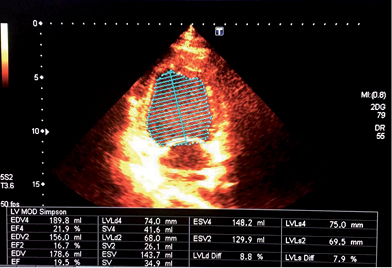

The patient was admitted with an initial diagnosis of pneumonia, being placed under an antibiotic therapy with levofloxacin 750 mg IV q24 hrs, along with oseltamivir, nebulized salbutamol, and budesonide. During his third day of stay he presented a sudden severe worsening of his clinical condition, with increased polypnea, tachycardia, dizziness and chest pain, which required the initiation of non-invasive mechanical ventilation, along with a transfer to the intensive care unit (ICU). The electrocardiogram (Figure 2), reported left ventricular hypertrophy as the most notable abnormality. A thorax CAT scan was performed (Figure 3), which showed signs of acute pulmonary edema. Suspecting a cardiopathy, an echocardiogram was performed (Figure 4), which showed a depressed ejection fraction of 19%, along with severe generalized hypokinesis.

Figure 4: Transthoracic echocardiography, with measurement of the ejection fraction (EF) through Simpson’s method, which shows EF of 19%.